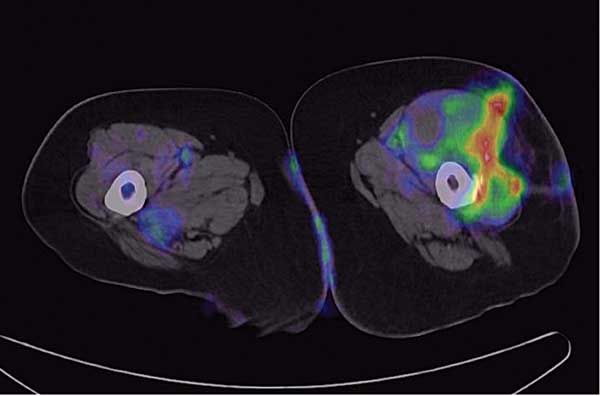

Positron emission tomography/CT performed after bronchoscopy demonstrated a lower lobe predominance with increased 18-fluorodeoxyglucose activity in the lower lobe and a maximum standardized uptake value (SUV) of 24.4. An unexpected finding was a soft tissue mass within the anterior musculature of the left thigh measuring 4.4 × 7.4 cm with a maximum SUV of 3.2 (Figure 3). A CT scan of the head without contrast was also obtained at this time and showed no evidence of metastatic lesions.

Figure 3–An unexpected finding on a positron emission tomography/CT scan was a soft tissue mass within the anterior musculature of the left thigh measuring 4.4 × 7.4 cm with a maximum standardized uptake value of 3.2.